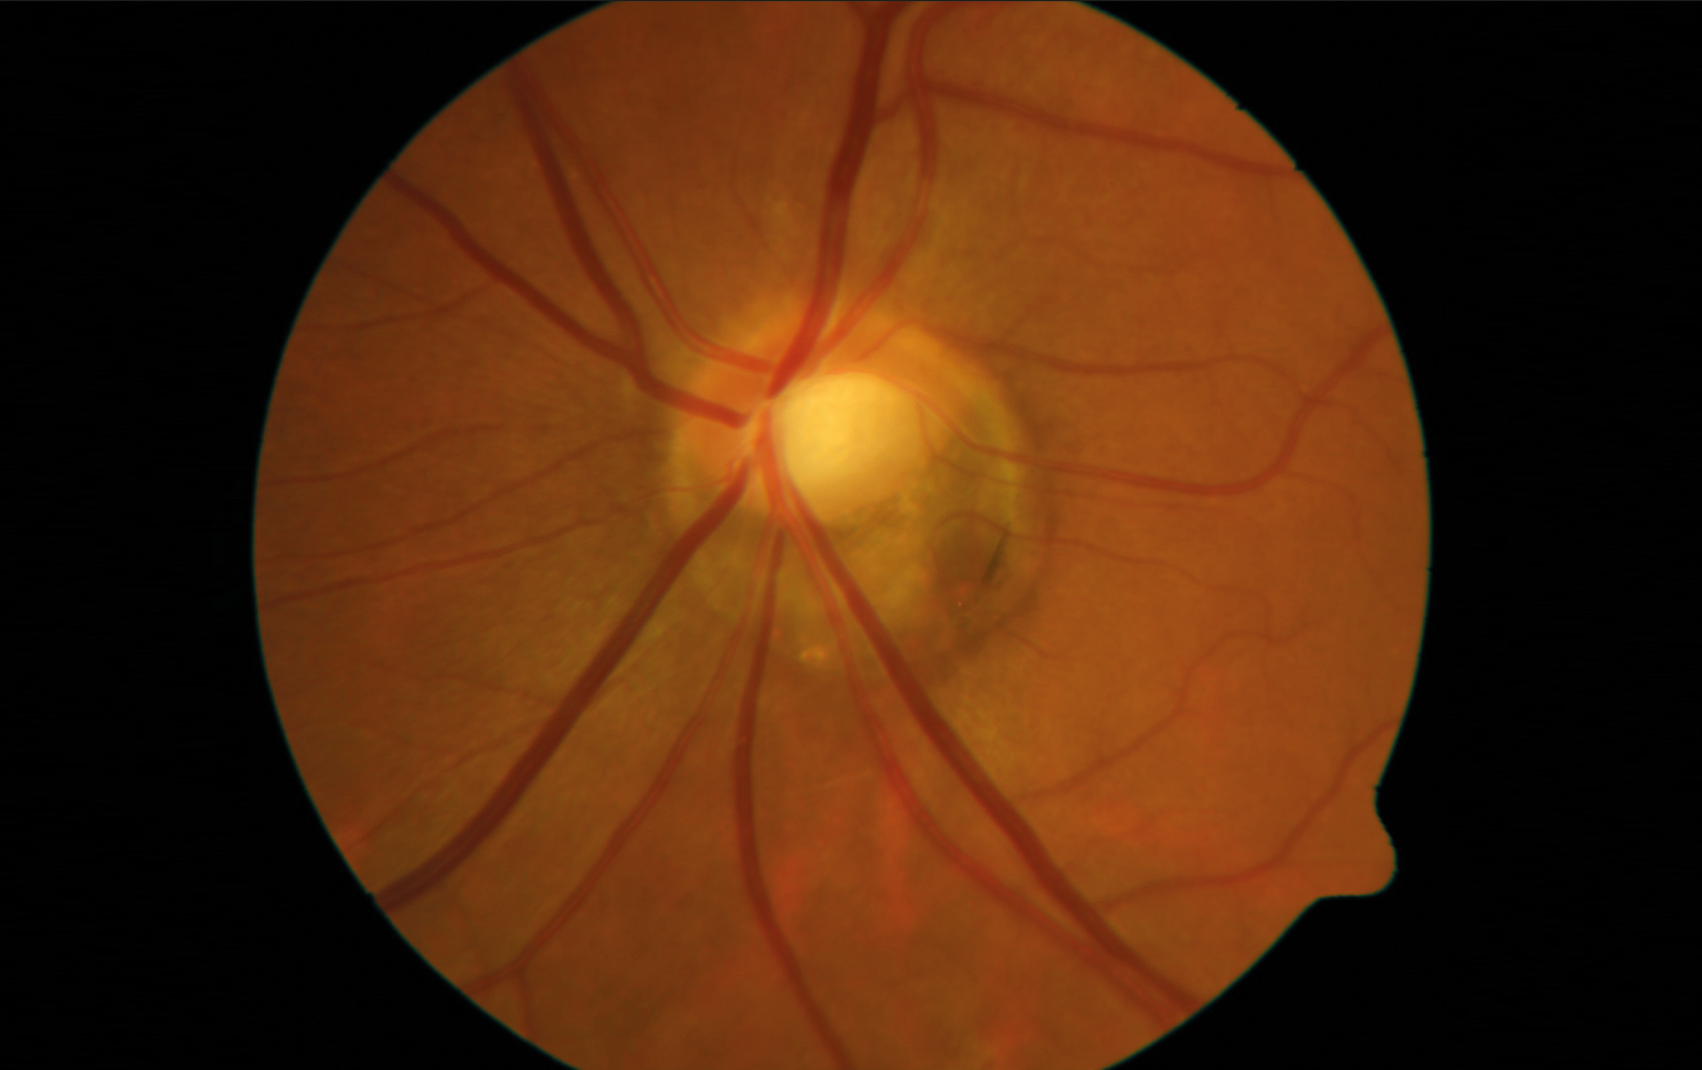

Figures 2A et 2B. Rétinophotos d’un patient myope fort - 16,00 OD (A) et - 17,50 OG (B) présentant un glaucome traité par trithérapie. Noter la présence d’une atrophie choriorétinienne diffuse, de staphylomes péripapillaires et maculaires des 2 côtés, ainsi qu’une dysversion papillaire plus marquée à gauche.

Figure 1. Papille de l’œil gauche présentant une inclinaison typique vers le quadrant temporal inférieur, ainsi qu’une rotation majeure. Notez la vaste zone d’atrophie péripapillaire dans la partie inférieure ; en cas de glaucome, cette zone est généralement la première touchée.